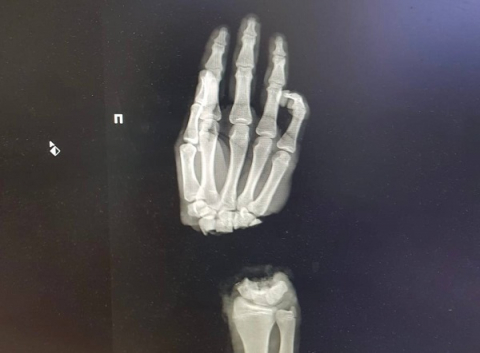

Юноша был доставлен в столицу Приволжья 1 марта из Коврова Владимирской области. Он случайно отрубил себе правую кисть, когда колол дрова. В тот же день нижегородские хирурги провели операцию по реимплантации конечности.

На данный момент подросток находится в обычном отделении, его состояние оценивается как стабильное. В ближайшее время пациенту предстоит еще несколько оперативных вмешательств, однако уже сейчас кровоснабжение руки восстановлено.

Фото: ПИМУ